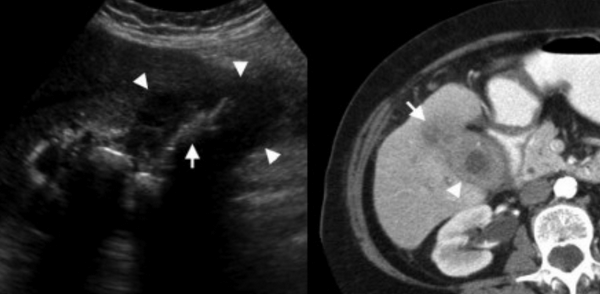

УЗИ и КТ желчного пузыря. Ксантогранулематозный холецистит. Слева на УЗИ визуализируется (помечено стрелками) утолщение стенки желчного пузыря с интрамуральным включением и с камнем в просвете органа. Справа на КТ выявляется утолщение стенки с гиподенсными включениями.

Выше представлено КТ пациента 71 года с ксантогранулематозным холециститом. Постконтрастное КТ. Визуализируется утолщение стенки желчного пузыря с включениями, которые соответствуют абсцессу или фокусам воспаления.

УЗИ (слева) и КТ (справа) желчного пузыря. На УЗИ ярко выраженное утолщение стенки желчного пузыря (указаны белыми стрелками). Множественные камни в просвете желчного пузыря (указано стрелкой). Компьютерная томография с контрастным усилением. На КТ визуализируются утолщение стенки с внутристеночными гиподенсными включениями. На КТ также выявлено, что процесс распространился на печень (указано стрелкой).